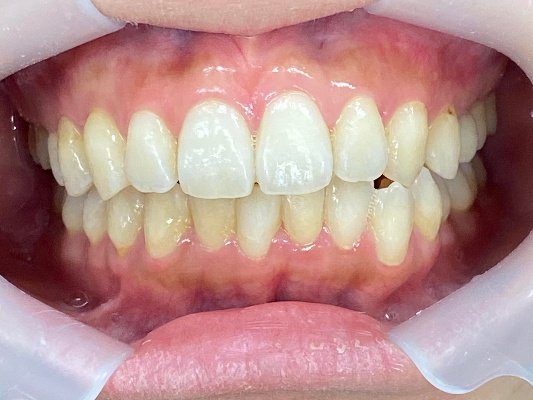

上下前歯の歯並びがガタガタしているのが気になる、きれいにしたいとのご希望で来院されました。

来院時の歯並び写真